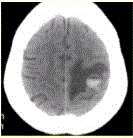

问题 患者女,55岁,右侧肢体无力3d。头颅CT显示如下图。 根据CT表现,可能的诊断为

选项 A.急性脑血肿 B.转移瘤伴出血 C.胶质瘤伴出血 D.少枝胶质细胞瘤伴出血 E.血液系统病变伴脑出血 F.脑脓肿 G.血管畸形伴出血

答案 ABCEG